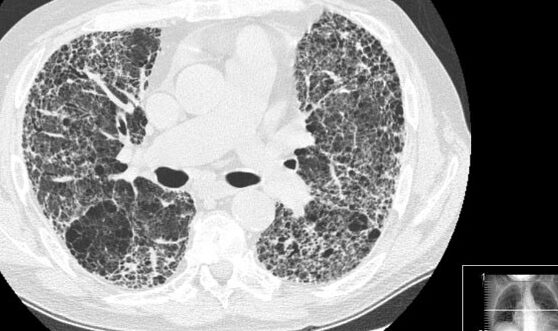

El diagnóstico de la fibrosis pulmonar se realiza mediante la evaluación de los síntomas, el historial médico, los hábitos de vida y un examen físico realizado por un neumólogo. También se pueden realizar diferentes pruebas para confirmar el diagnóstico, como la oximetría para medir los niveles de oxígeno en sangre, análisis de sangre y pruebas de función pulmonar para evaluar la capacidad respiratoria, y radiografías o tomografías computarizadas para evaluar los daños en los pulmones. Es importante buscar atención médica ante la presencia de estos síntomas y realizar todas las pruebas necesarias para llegar a un diagnóstico preciso.